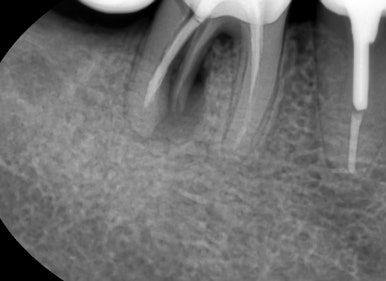

엑스레이를 촬영 해 보니 이미 큰 어금니는 싱가폴에서 많이 발치한 상태 였고

이번에는 작은 어금니가

가로로 파절된 것이 의심되는 확인할 수 있었습니다

치아 뿌리가 가로로 파절된 선이 보입니다

치아뿌리가 가로로 파절된 선이 보입니다

보이시나요?

표시해드릴게요 ↓